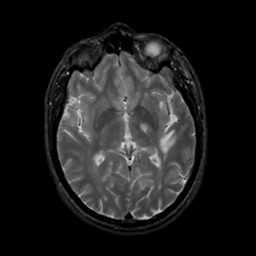

MR Study #20 October 6, 1991 -- Slice #25